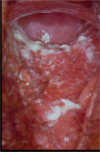

- Erythematous cervix with punctate appearance

Trichamonas vaginitis

Investigations

wet prep to see the Trichomonads. They are flagellated protozoae

Management

Usually use oral Metronidazole or Tinidazole, except you can’t use these in pregnancy (use Clotrimazole in pregnancy)

It is a genuine STD, so you must treat both partners